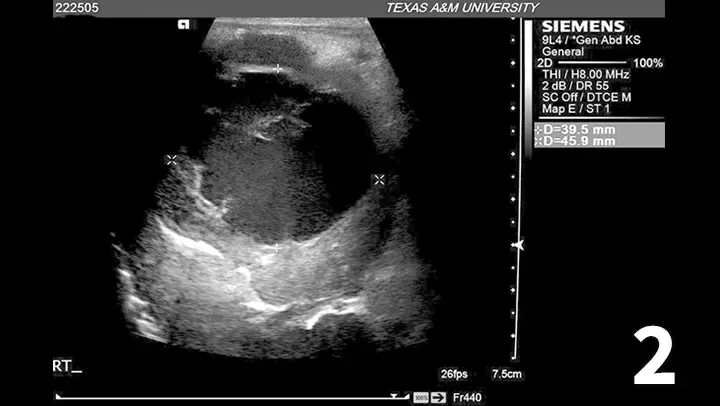

Cavitary region within mass in the right liver lobe, composed of mixed highly echogenic and hypoechoic fluid and a few small, hyperechoic septae. The cavitation measures ~4.0 x 4.5 cm between the ‘x’ symbols.

An abdominal ultrasound was also pursued to investigate possible sources of thromboembolic disease and to further evaluate the hepatomegaly identified on abdominal radiographs. A 4-5–cm diameter, ill-defined mass with poor intraparenchymal blood flow and a large cavitary region was identified in the right liver lobe (Figure 2).